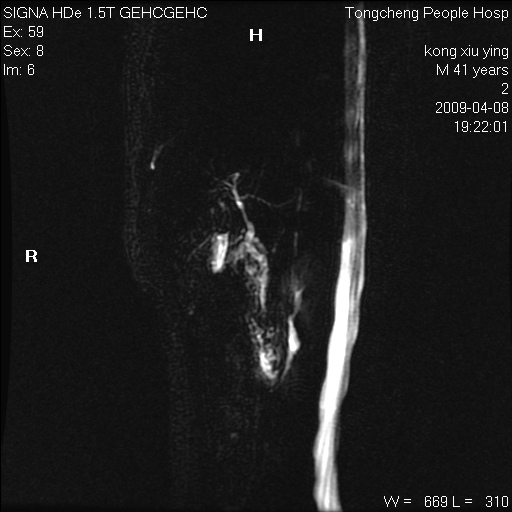

标题: CL1008:【经典】胆囊石榴籽样结石。

女,41岁。健康体检——彩超提示:胆囊显示不清。平素健康,无不适感。

腹部mr扫描及mrcp,图像如下: